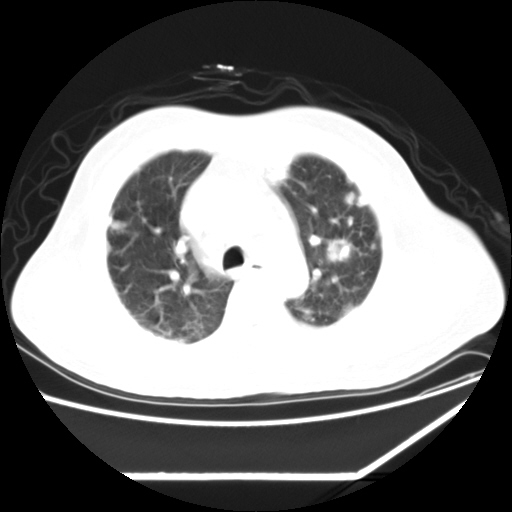

男,57,畏寒,发热

双肺多发结节样病灶,部分内见透光区,纵隔内见淋巴结肿大。结核临床如有畏寒,高热,白细胞增高首先考虑迁徙性肺脓肿(多是金黄色葡萄球菌感染)。

注意除外转移瘤。

畏寒发热,首先考虑血源性肺脓肿,结合临床,抗炎后复查排除转移瘤等。

血源性肺脓肿,除外转移瘤